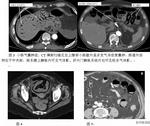

腸道氣囊腫症1.腹部平片 採取臥位及直立位平片,攝片前宜清潔灌腸。當氣囊小、數量又少時,多無特徵性表現,若氣囊大而多,尤其位於漿膜下,則可見:①充氣腸曲的邊緣可見聚簇或波浪狀的連續囊狀透光區,大小不等,自粟粒至葡萄大小,直徑通常1~2cm;②氣囊破裂形成氣腹時,立位片可見膈下游離氣體;③間位腸曲征(Chilaiditi)是氣腹時氣體積於橫膈和肝或胃底之間,使膈升高,肝或胃底下降,造成相當大的間隙,充氣的腸曲易上升而進入間隙內,形成間位腸曲,氣囊腫的腸曲更易形成間位,使腸壁的確良囊狀透光區顯示更清晰,此征出現對該病診斷幫助甚大。

腸道氣囊腫症病理檢查:迴腸一段,長18cm,病變長15cm,病變腸壁明顯增厚,腸腔狹窄,切面腸壁正常結構消失,全層均由大量的大小不等的囊泡樣腫物構成,從1毫米到數厘米相聚呈葡萄狀(附圖)互相不通,切開囊泡有氣體溢出,隨之囊泡萎縮。鏡下觀察:腸壁各層均見有大小不等的囊腫,囊壁由纖維組織構成,部分內壁襯覆一層扁平上皮,囊與囊之間纖維組織增生,內有多少不等的急慢性炎細胞浸潤。

病理診斷:小腸氣囊腫症

討論:小腸氣囊腫症是一種罕見的腸道疾病。本病以腸壁漿膜下出現單個、多個或呈叢狀的含氣的囊腫為特徵。大部分氣囊腫病伴有胃腸道其它疾病,但發生原因尚不清楚,多數學者認為本病是產氣性非致病菌所致。